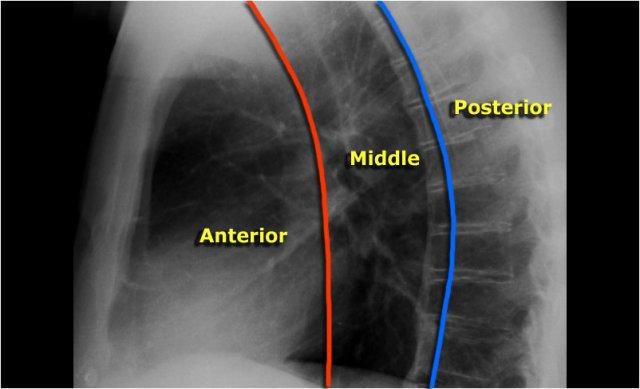

Tư thế nghiêng

Trên phim X-quang ngực tư thế nghiêng, các bờ tim cần được xác định rõ ràng, và tĩnh mạch chủ dưới (IVC) thường có thể thấy đổ vào nhĩ phải.

Khoang sáng sau xương ức

Khoang sau xương ức bình thường chứa phổi có khí và do đó phải có hình ảnh thấu quang (tối trên phim), kéo dài xuống dưới đến mức thất phải tiếp xúc với xương ức (mũi tên đen nhỏ).

Bất kỳ hình mờ nào trong khoang sau xương ức phía trên đều đáng ngờ về tổn thương trung thất trước hoặc khối xuất phát từ các thùy trên của phổi.

Dấu hiệu cột sống

Khi đánh giá các thân đốt sống trên tư thế nghiêng, chúng phải có hình ảnh thấu quang (tối hơn) tăng dần từ trên xuống dưới do lượng phổi có khí chồng lên ngày càng nhiều (mũi tên trắng).

Nếu các đốt sống ngực dưới có hình ảnh đậm bất thường, điều này có thể gợi ý bệnh lý ở các thùy dưới, chẳng hạn như đông đặc hoặc khối — đây được gọi là dấu hiệu cột sống.

Đánh giá Cơ hoành

- Vòm hoành phải phải được nhìn thấy rõ ràng ở phía trước đến tận thành ngực (mũi tên đỏ), thể hiện ranh giới giữa phổi có khí và mô mềm ổ bụng.

- Vòm hoành trái thường chỉ nhìn thấy đến điểm tiếp giáp với bóng tim (mũi tên xanh lam), phía ngoài điểm đó ranh giới bị mất do tỷ trọng tương đương giữa tim và các tạng bụng phía trên.